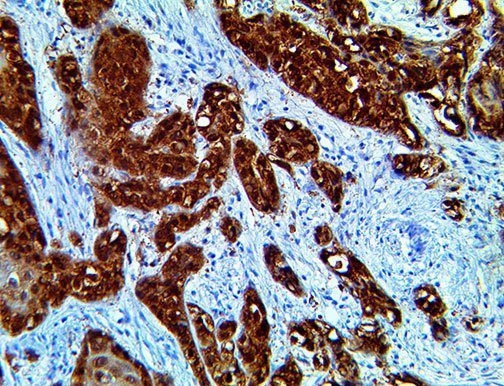

The first cytokines released are interleukin 1β (IL-1β) and tumor necrosis factor-α (TNF-α), which attract a variety of circulating white blood cells (WBCs) to the infection site, including neutrophils, monocytes, macrophages, and natural killer (NK) cells. This response, along with the antipathogenic chemicals released by these cells (i.e., complement), comprise the innate immune response. These cells directly attack the invading pathogen and also release additional cytokines, chief among them interleukin-1 and 6 (IL-6). IL-6 is essential for invoking the adaptive immune response, which calls T-cells, B-cells, and T helper (Th) cells to the infection site. IL-6 also stimulates further recruitment, proliferation and activation of macrophages.

It is the ICU physician who is most likely to witness one of the deadliest manifestations of the abnormal immunological response, the cytokine storm syndrome (CSS). This response is also referred to by some as the cytokine release syndrome (CRS). CSS is characterized by continuous activation and expansion of macrophage and lymphocyte populations, which secrete large amounts of cytokines, causing the cytokine storm. This massive cytokine release is akin to hemophagocytic lymphohistiocytosis (HLH) disease, a syndrome characterized by initial unchecked and persistent activation of cytotoxic T lymphocytes and NK cells.

This activation induces inflammatory monocytes to highly express IL-6, starting a localized and then systemic cascade effect that results in hyperproduction of IL-6, which accelerates the inflammatory process. Because IL-6 also increases vascular permeability, excessive levels cause blood vessels to become very leaky. This, along with clotting factors released from vascular endothelial cells, stimulates the coagulation cascade, resulting in microthrombosis (tiny clots), which leads to ischemia and tissue death of the kidney, intestines, heart, liver, brain and extremities.